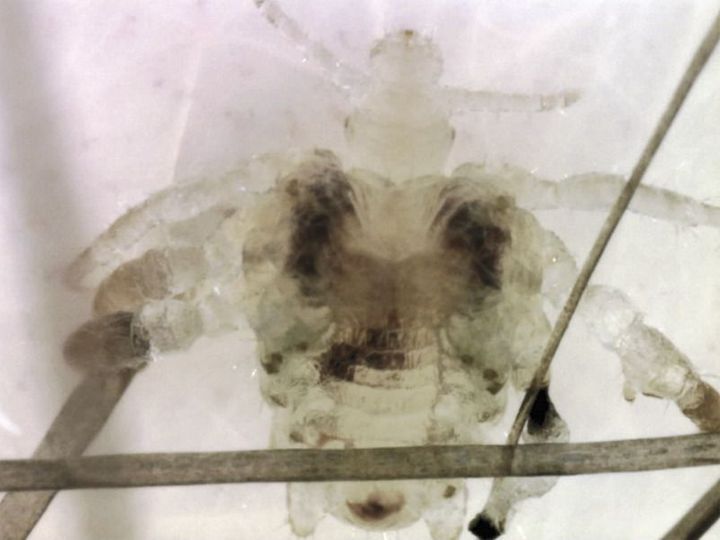

A 56-year-old man presented with a 3-month history of generalized pruritus. Physical examination was notable for small black dots between body hairs on the abdomen and pelvis. Dermoscopic examination of the abdomen revealed a pubic louse, which is smaller than the head louse and has a round form and thick back legs with large claws. Video obtained with the use of epiluminescence microscopy provided a magnified view of the characteristics of the parasite (seeΒ video). The pubic louse, which is also known as the crab louse because of its morphologic features, can cause intense pruritus. This patient was treated successfully with shaving of the abdomen and pubic area and with a single 8-hour application of 5% permethrin cream.